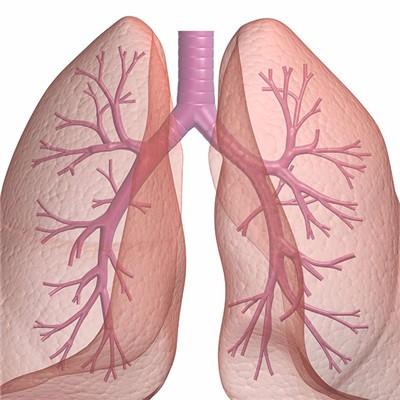

My brother kept coughing these two days, and he also said that he had chest tightness and abdominal pain, and felt that the situation was not right. We went to the hospital for examination. As a result, the doctor said that his brother was diagnosed with lung cancer, and timely treatment was the most important thing. Next, I'd like to talk about the method of completely cured lung cancer?

First, chemotherapy is the main treatment for lung cancer, more than 90% of lung cancer need chemotherapy. The curative effect of chemotherapy on small cell lung cancer is positive in both early and late stage, and even about 1% of early small cell lung cancer is cured by chemotherapy. Chemotherapy is also the main treatment for non-small cell lung cancer. The tumor remission rate of chemotherapy for non-small cell lung cancer is 40% - 50%.

Second, radiotherapy is the best for small cell lung cancer, followed by squamous cell carcinoma and adenocarcinoma. The radiation field of lung cancer should include the mediastinum of primary tumor and lymph node metastasis. At the same time, it should be supplemented by drug treatment. Squamous cell carcinoma has moderate sensitivity to radiation, the lesions are mainly local invasion, metastasis is relatively slow, so radical treatment is often used. Adenocarcinoma is not sensitive to radiation and easy to metastasize, so radiotherapy alone is rarely used.

Third: according to the different purposes of treatment, it can be divided into radical treatment, palliative treatment, preoperative neoadjuvant radiotherapy, postoperative adjuvant radiotherapy and intracavitary radiotherapy. Surgical treatment is the first choice and the most important treatment for lung cancer, and it is also the only treatment that can cure lung cancer. The purpose of surgical treatment of lung cancer is: to completely remove the primary focus and metastatic lymph nodes of lung cancer, to achieve clinical cure; to remove most of the tumor, to create favorable conditions for other treatment, namely tumor reduction surgery.

For patients with lung cancer, cough and chest tightness will often appear. If not treated in the early stage, hemoptysis will appear in the later stage. Surgery and chemotherapy can be used to control the proliferation and differentiation of cancer cells. In addition, some immunity enhancing drugs can also be taken.